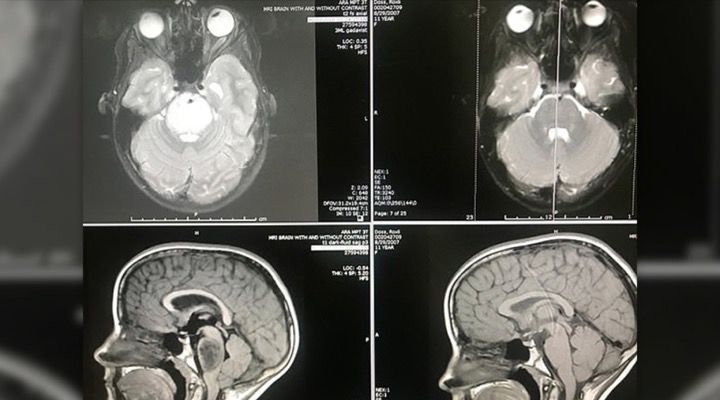

11-Year-Old Girl’s Inoperable Brain Tumor Mysteriously Vanishes Without a Trace